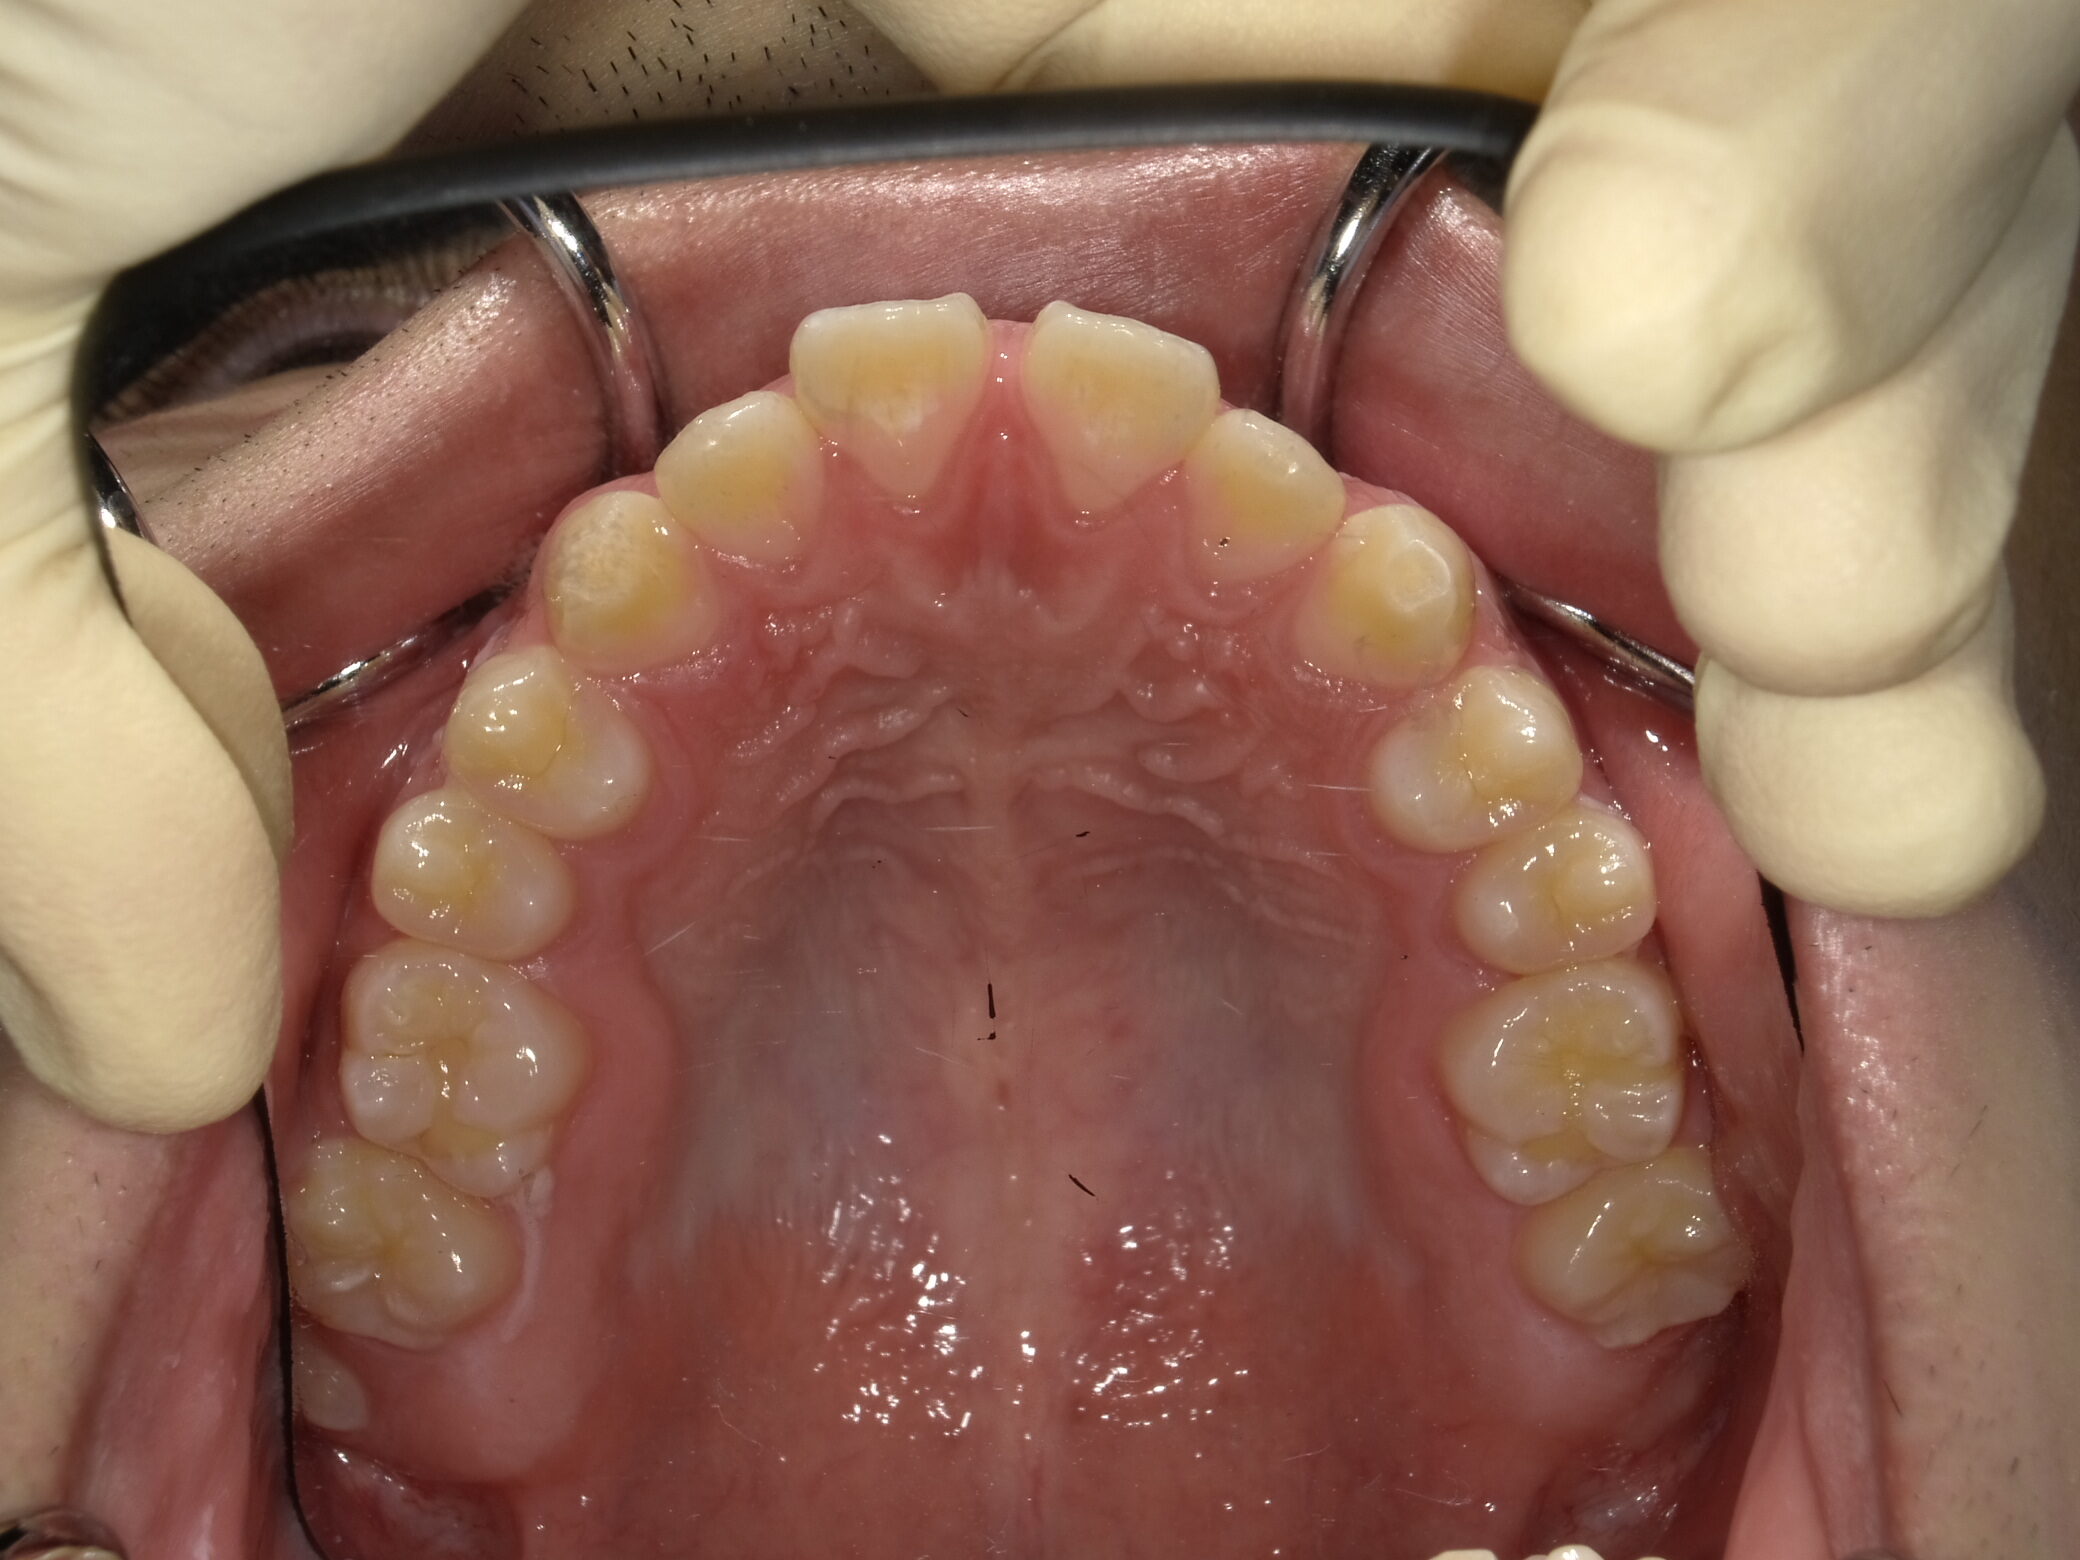

| 症例分類 | 上下顎前突 |

|---|---|

| 主訴 | 前歯が出ていて、口が閉じにくい |

| 年齢 | 20歳0ヶ月 |

| 性別 | 男性 |

| 抜歯部位 | 上下顎両側第一小臼歯 |

| 使用装置 | 歯の表側からのマルチブラケットによる矯正装置 |

| 治療期間 | 2年10ヶ月 |

| 保定装置 | 取り外し式保定装置 |

| 費用 | 相談料0円、検査料55,000円 動的矯正治療費935,000円 調整料6,600円×28回分 保定装置料0円 |

| リスク・注意点 | 上下の個々の歯の大きさに対して上下の顎が小さく歯が並ぶスペースが不足したために上下の前歯が前方に傾斜して、上下顎前突が生じています。これらを改善するために、上下顎両側第一小臼歯を抜歯して、このスペースを用いて歯を排列しました。歯の動き方には個人差があり、予想された治療期間が延長する可能性があります。 治療中は矯正歯科装置が歯の表面に付いており、歯が磨きにくくなるため、むし歯や歯周病が生じるリスクが高まります。ハミガキを適切に行ってお口の中を常に清潔に保ち、さらに、かかりつけ歯科医に定期的に受診することが大切です。 顎間ゴムの使用状況、定期的な通院など、矯正歯科治療には患者さんの協力が必要であり、それらが治療結果や治療期間に影響します。 治療の経過によっては当初予定していた治療計画を変更する可能性があります。 歯を動かすことにより歯根が吸収することがあります。 保定装置の装着時間が十分確保できない場合、歯並びや、咬み合せの「後戻り」が生じる可能性があります。 |